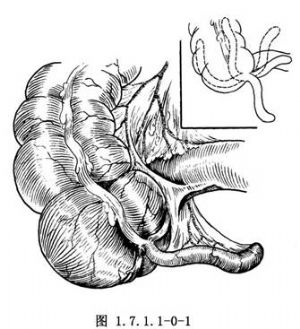

闌尾爲一盲管,其根部位於盲腸末端內後3條結腸帶匯合之處,與盲腸相通。尖端遊離,可伸向任何方向。常見的部位有迴腸前位或後位、盲腸下位、盲腸後位、盲腸外側位等(圖1.7.1.1-0-1)。所以,在闌尾手術時,應先找到盲腸,順結腸帶向下尋找,在3條結腸帶的匯合處,即能找到闌尾根部。闌尾系膜中有闌尾動脈和靜脈。闌尾動脈起於回結腸動脈,爲一終末支,一旦血循環受阻,極易發生闌尾壞疽;闌尾靜脈通過回結腸靜脈到腸繫膜上靜脈入門靜脈。因此,在闌尾化膿時,有可能導致門靜脈炎或肝膿腫。